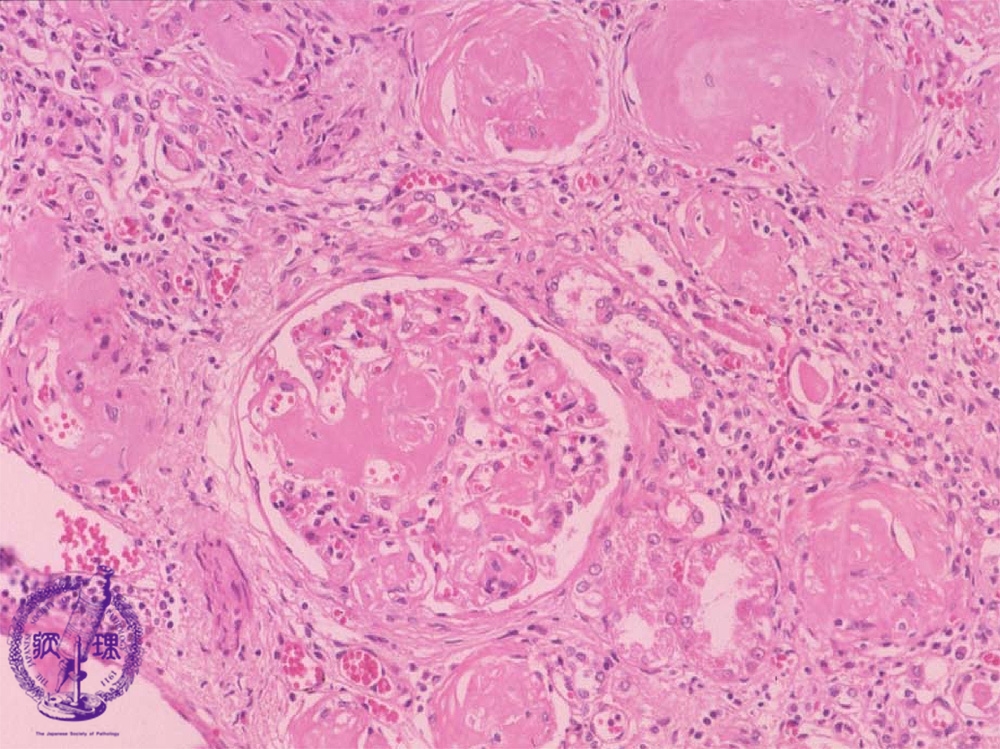

- ★(15)Renal amyloidosis

Microscopic findings (HE, middle power view):Eosinophilic and homogenous substance (amyloid) is deposited in the glomeruli and perivascular regions (yellow dotted lines).